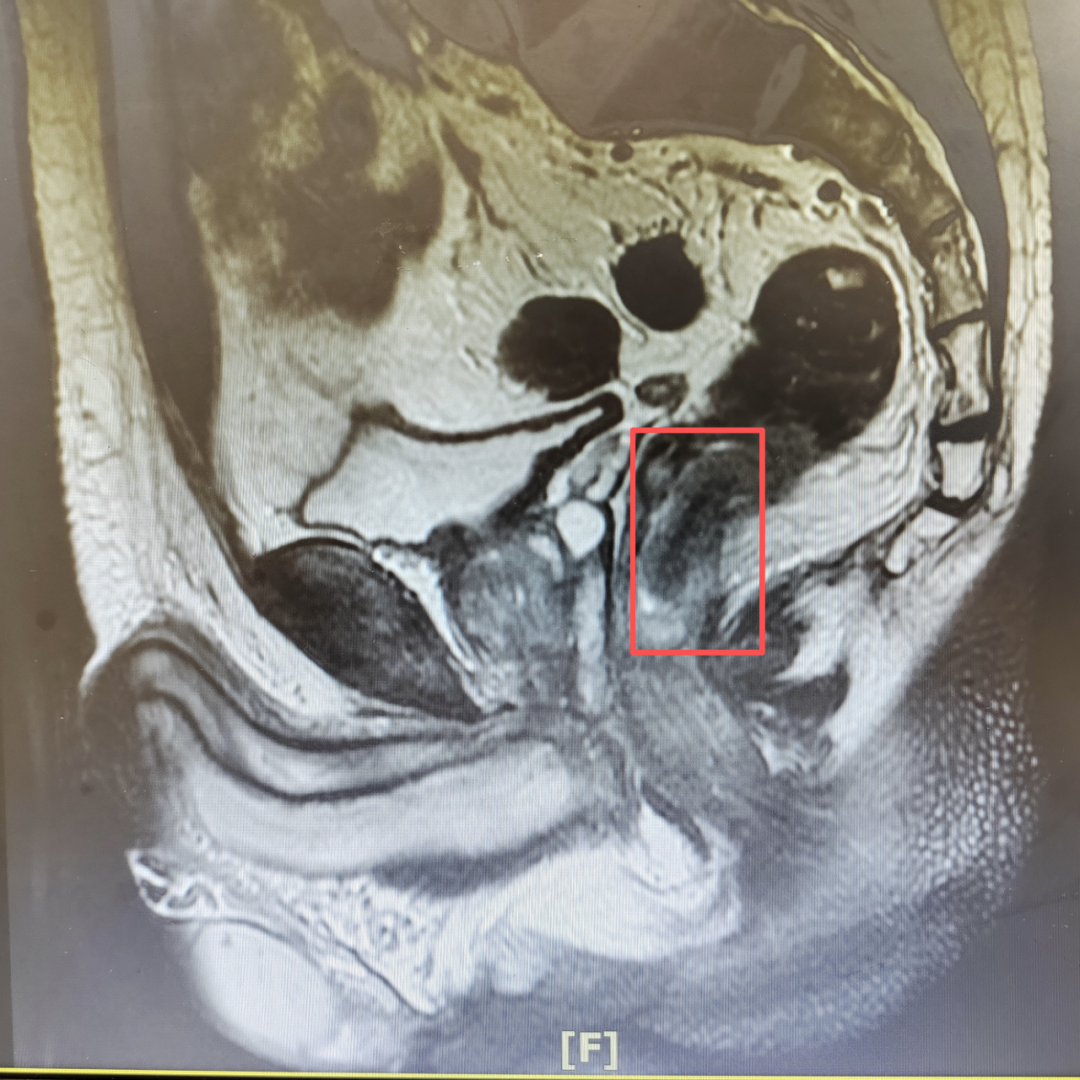

随即到当地医院检查,诊断为“超低位直肠癌”,肿瘤的下缘距离齿状线(直肠粘膜与肛管皮肤之间的交界线)仅2厘米。

接诊后,张超教授团队立即结合全面的检查报告,综合分析王大叔病情。由于发现较早,肿瘤不大且未浸润肛门外扩约肌,患者身体基本情况较好,肛门功能良好。

张超教授团队认为可尽快为其开展腹腔镜辅助经括约肌间直肠癌根治术(ISR)。这一消息对于王大叔一家,像黑暗中的一束光。

盆腔狭小的空间里结构复杂,有大量的神经、血管、肌肉和筋膜。手术对术者技术要求非常高。

张超教授、徐建华教授团队借助腹腔镜,通过腹部几个不到1厘米的小孔和肛门这个天然通道,充分游离肿瘤,保证了肿瘤的完整切除,且最大限度保护自主神经及肛门括约肌功能。手术历时4个小时顺利完成。